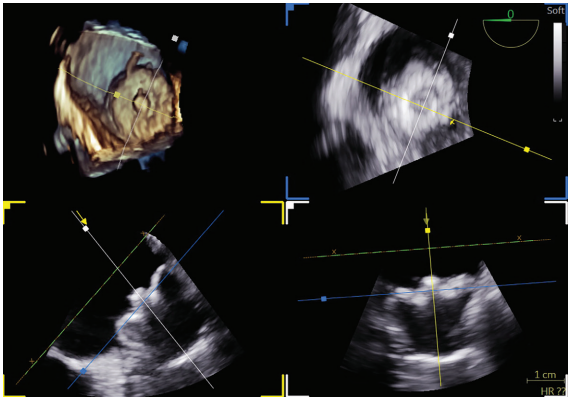

Intraprocedural imaging and mapping were performed using 4D ICE via a 11 French venous sheath and 3D electroanatomic mapping to guide transseptal access, verify lesion delivery, and confirm optimal LAA device position, all under conscious sedation. The 4D ICE provided volumetric, high-resolution visualization of the LA and LAA in real time, while 3D mapping allowed detailed electroanatomic reconstruction and accurate lesion targeting with reduced reliance on fluoroscopy.

A transseptal catheterization was performed using the Faradrive Steerable Sheath (Boston Scientific) and Faraconnect dilator, along with VersaCross Access Solution (Boston Scientific), in the low to mid septum and slightly anterior position to facilitate the ablation and subsequent exchange for the Watchman TruSteer (Boston Scientific) delivery sheath for an optimal ablate-and-close procedure. LAA measurements obtained before ablation were 18 to 19 mm in 3 views (short-axis/mid LA, long-axis, and supramitral). No significant edematous change was observed in the limbus after ablation. A 27-mm Watchman FLX Pro LAAO device was selected, which completely sealed the LAA without residual leak on color flow imaging. Postdeployment measurements were 19 to 20 mm in 3 ICE views, including multiplanar reconstruction using the 4D ICE Nuvision Ultrasound Catheter (Johnson & Johnson MedTech). The patient tolerated the procedure without complications.